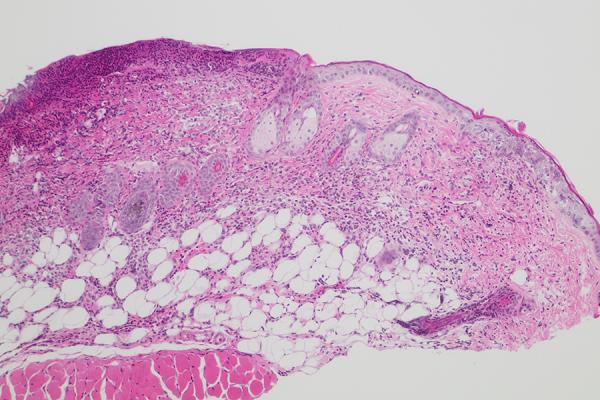

Image description: During active disease, herpes simplex virus (HSV) replication in skin epithelial cells (keratinocytes) causes cytopathic effects. The keratinocytes release cytokines that promote recruitment of immune cells, killing of infected cells, and viral restriction. The image shows a cross section of mouse skin stained with hematoxylin and eosin revealing these different stages of HSV infection.